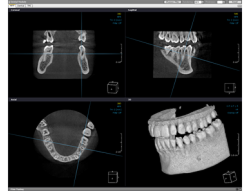

従来のレントゲンは2次元の平面図でしたが、歯科用CTでは、3次元で細部まで鮮明に映し出すことができるので、より正確な診断が可能となりました。

詳しくは、歯科用CTによる診断でより安全・正確な治療をページをご覧下さい。